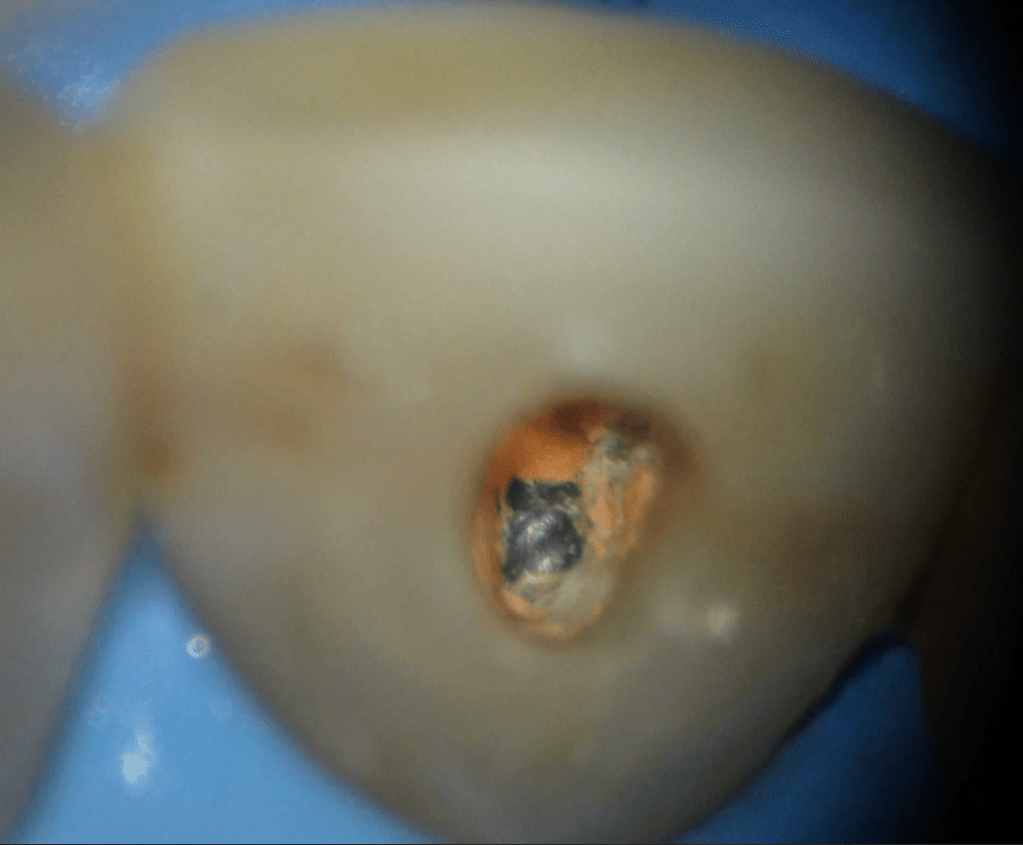

Fisura, remoción amalgama para explorar